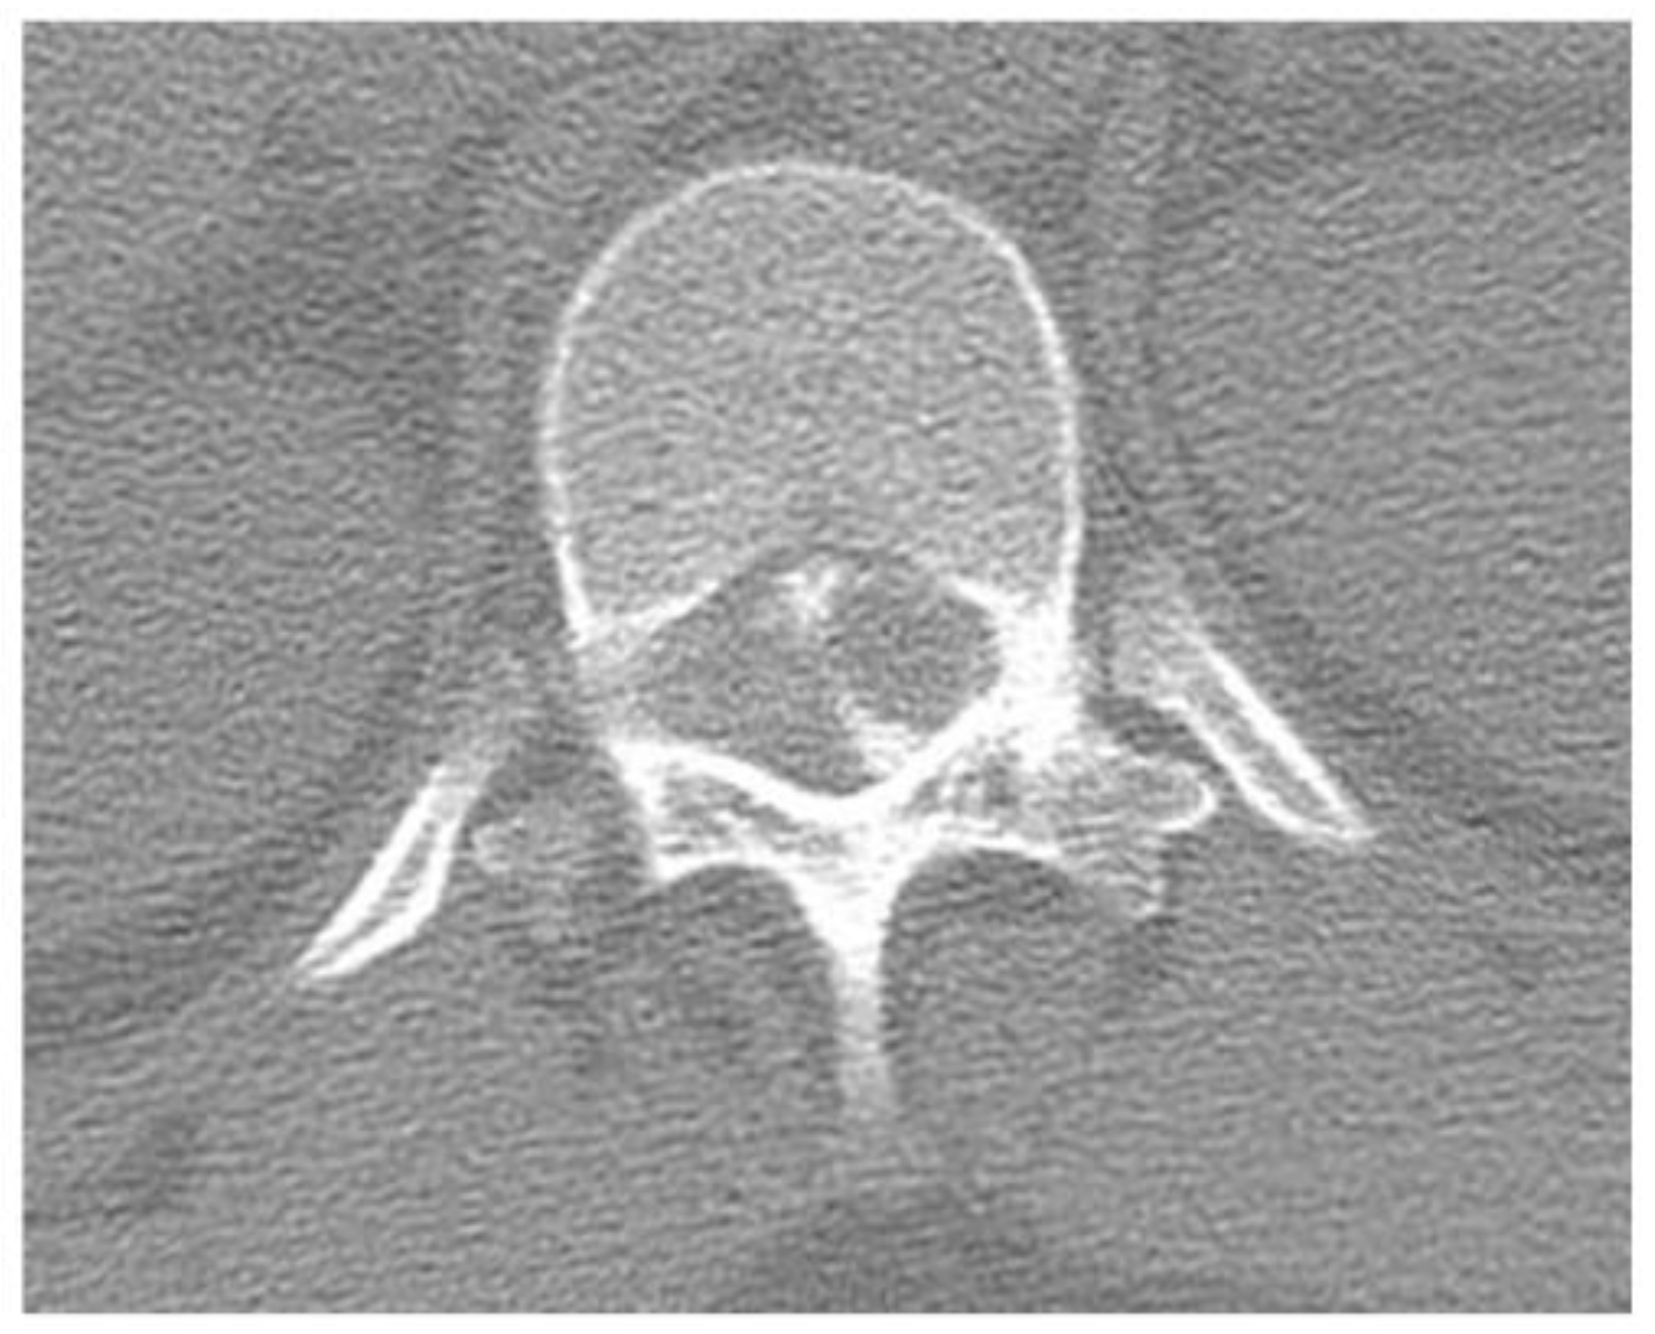

2.1. Case 1